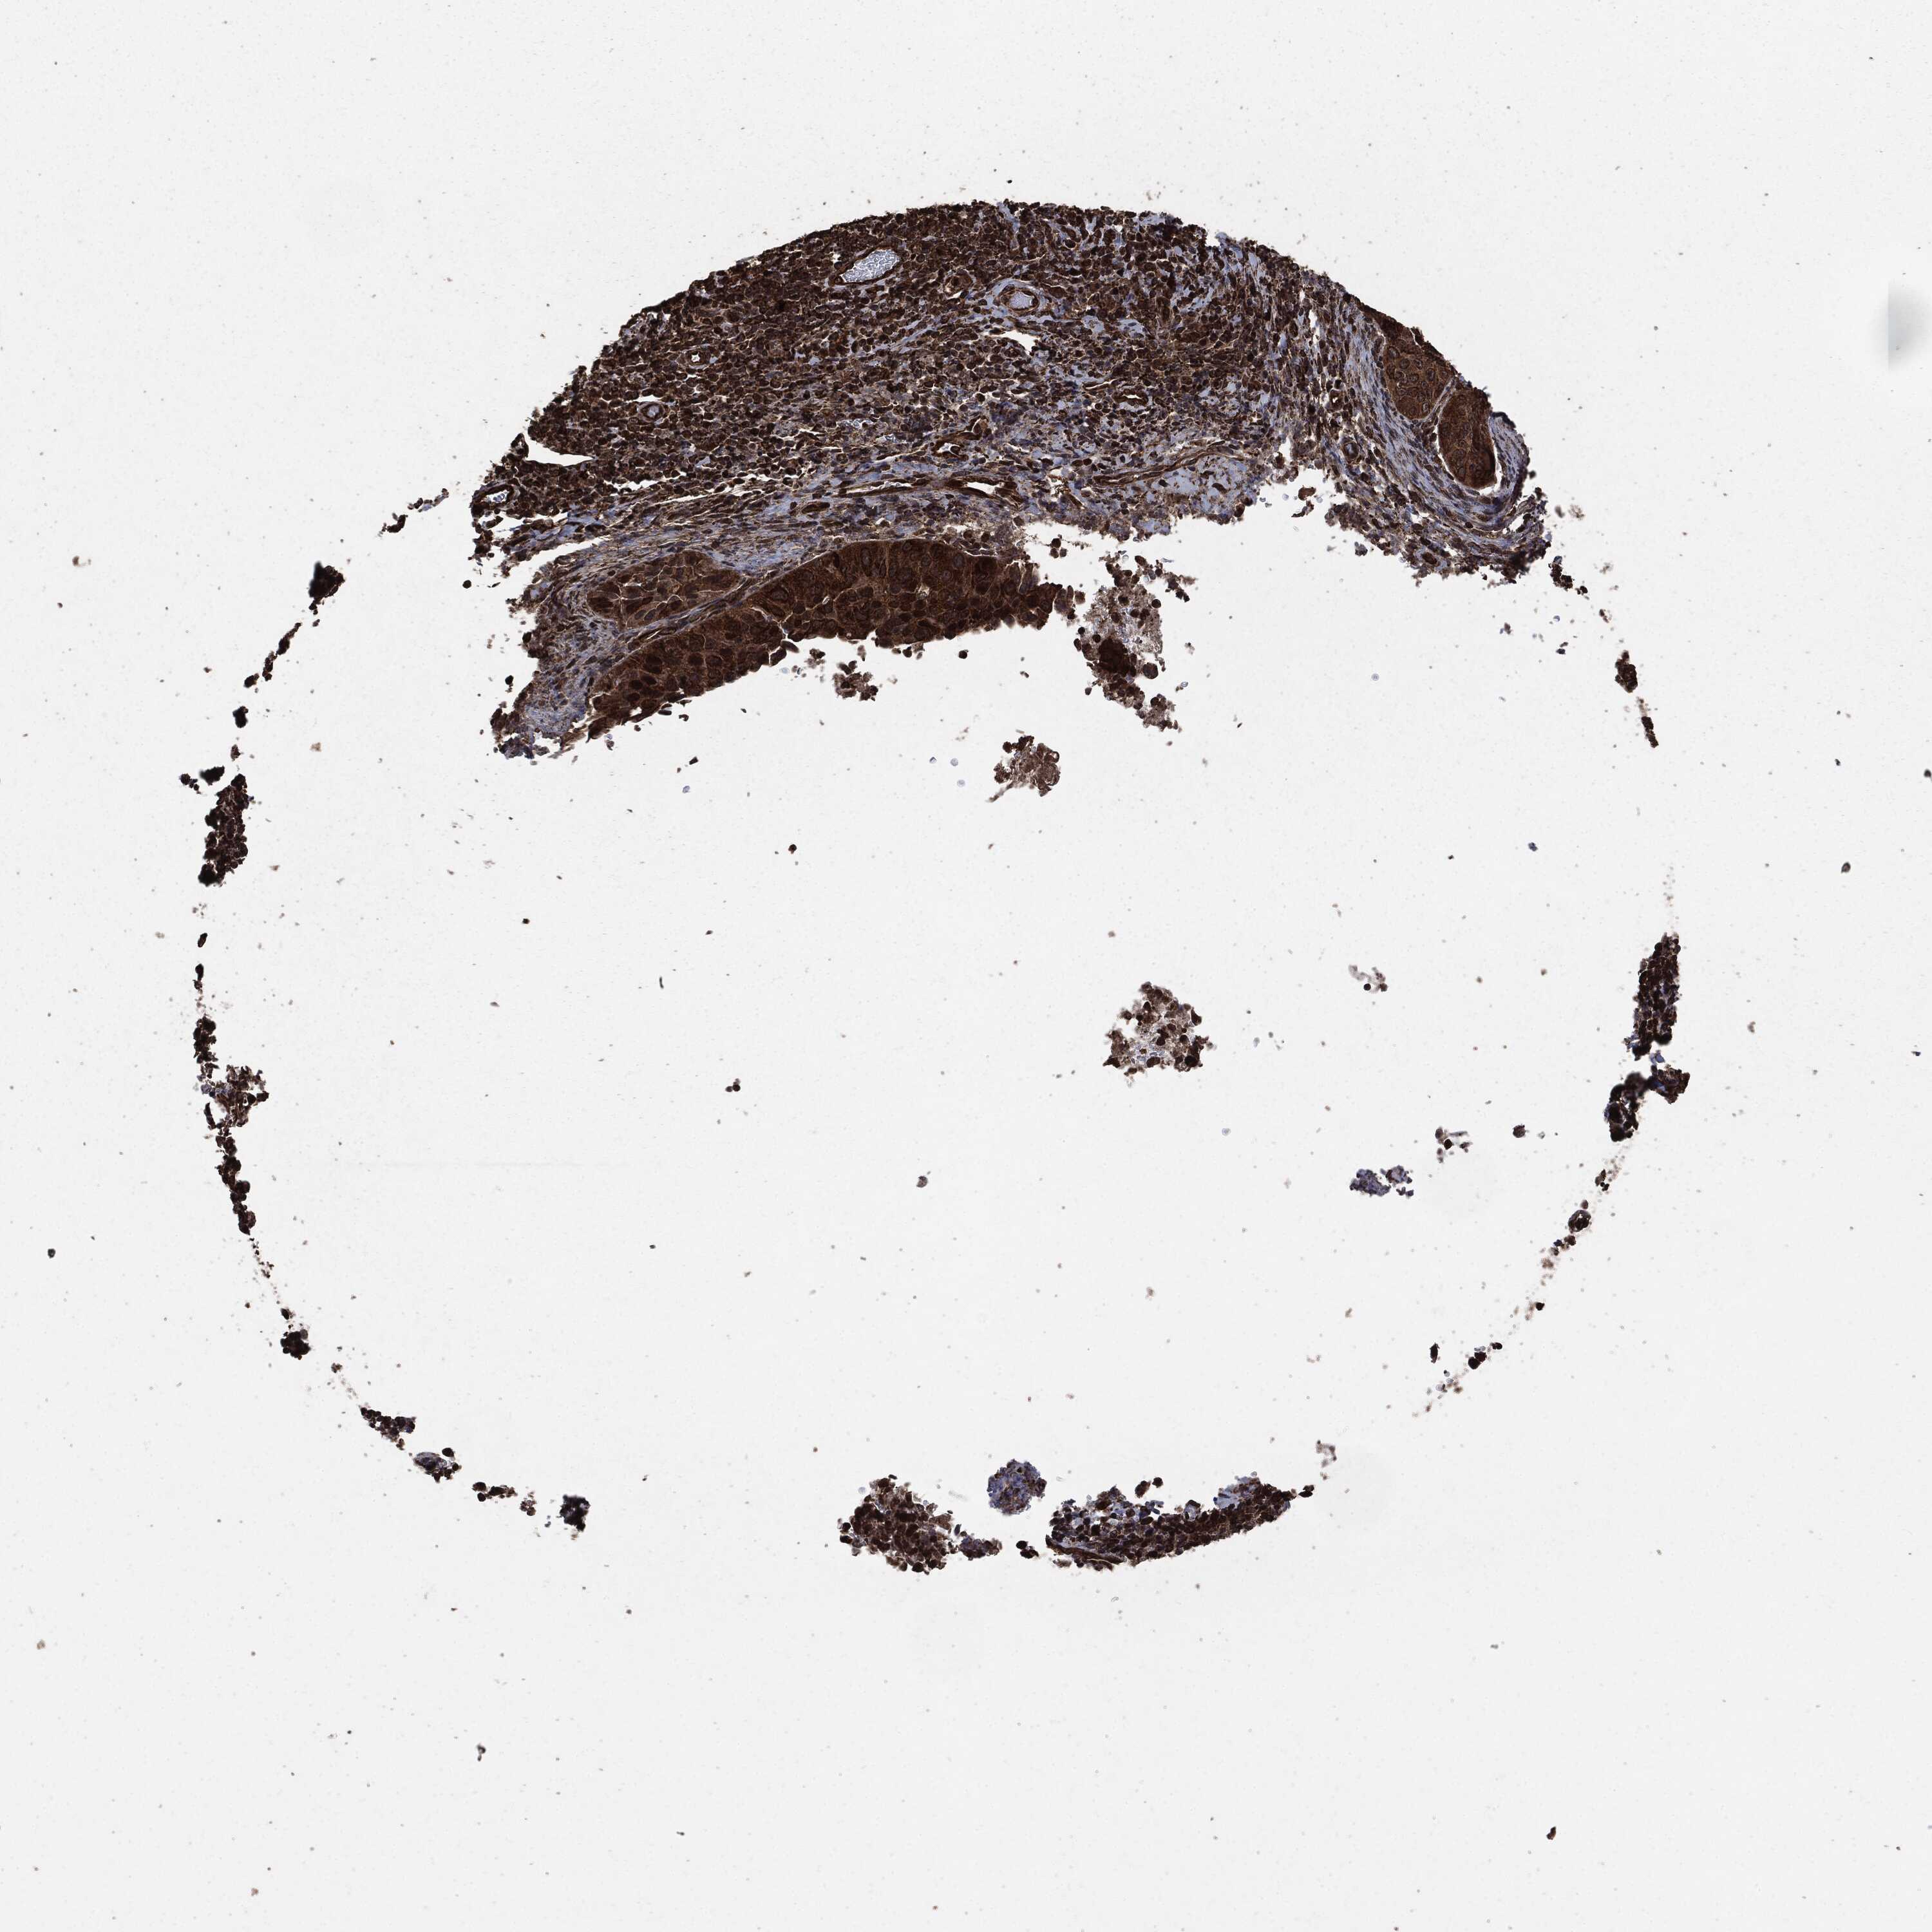

CERVICAL CANCER - Protein expressioni

A mouse-over function shows sample information and annotation data. Click on an image to view it in a full screen mode. Samples can be filtered based on level of antibody staining by selecting one or several of the following categories: high, medium, low and not detected. The assay and annotation is described here.

Note that samples used for immunohistochemistry by the Human Protein Atlas do not correspond to samples in the TCGA dataset.

Antibody stainingi

Antibody staining in the annotated cell types in the current human tissue is reported as not detected, low, medium, or high, based on conventional immunohistochemistry profiling in selected tissues. This score is based on the combination of the staining intensity and fraction of stained cells.

Each image is clickable and will lead to virtual microscopy that enables deeper exploration of all samples and also displays staining intensity scores, fraction scores and subcellular localization as well as patient and tissue information for each sample.

HPA001200

Staining

High

Medium

Low

Not detected

Intensity

Strong

Moderate

Weak

Negative

Quantity

>75%

75%-25%

<25%

None

Location

Nuclear

Cytoplasmic/membranous

Cytoplasmic/membranous,nuclear

Adenocarcinoma, NOS

Squamous cell carcinoma, NOS